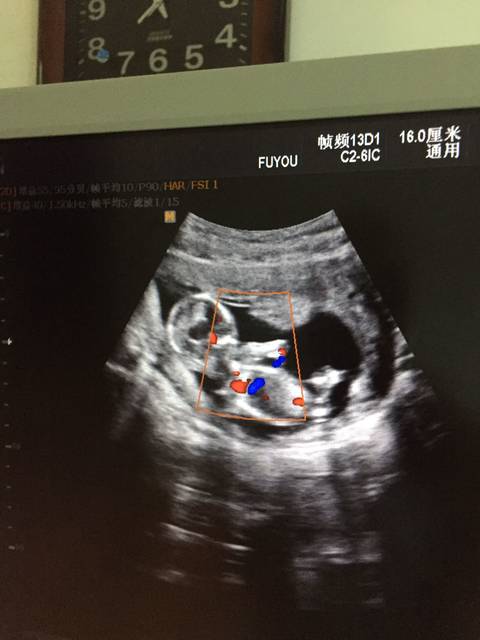

彩超

彩超,女性彩超

彩超图片 真实

彩超 男女

彩超怀孕

彩超是什么样的图片

彩超检查图